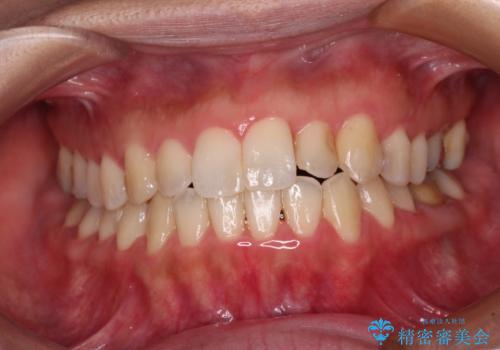

- 前歯の捻れを気にして来院された患者様です。

上顎前歯が捻れて前方に飛び出しており、下顎前歯もそれに沿うようにデコボコとなっていました。

IPR(歯と歯の間を削る処置)によりスペースを獲得して上下前歯のデコボコを改善し、インビザラインにて矯正治療を行うこととしました。

捻れていた前歯の形態が、先端が欠けていたり、一部むし歯処置により左右非対称の形態となっていたため、なかなかゴールが定まらず、治療期間がかかってしまいました。